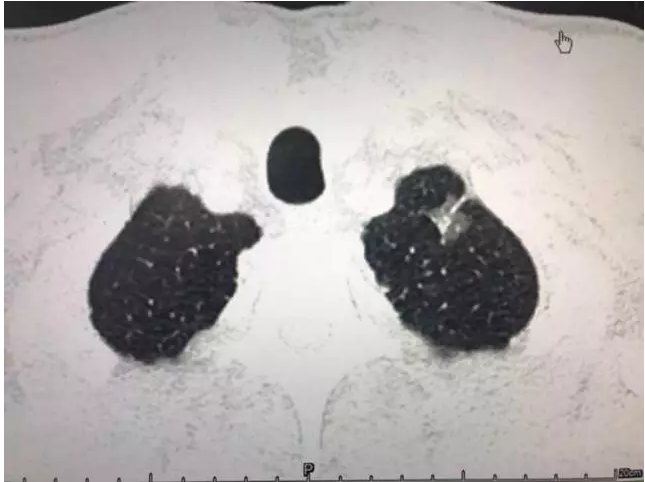

左上肺混合磨玻璃密度结节。一case oftoday 左上肺靠近胸膜可见一个混杂磨玻璃密度结节,形态不规则,瘤肺

形态不规则,密度不均匀,呈浅分叶患者现在主要是CT检查发现毛玻璃样结节的情况,并且,大小大于8毫米,